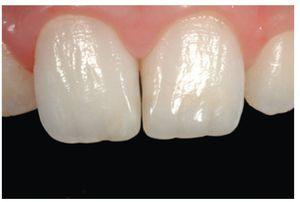

Figura 3 El caso terminado tras la reconstrucción con composite, realizada tras la cicatrización de los tejidos gingivales.